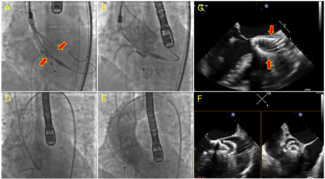

An 80-year-old man presented with dyspnea. Nine years earlier, he had undergone transcatheter aortic valve replacement with a 29-mm Evolut R self-expanding valve (Medtronic) following aborted surgical aortic valve replacement due to extensive...